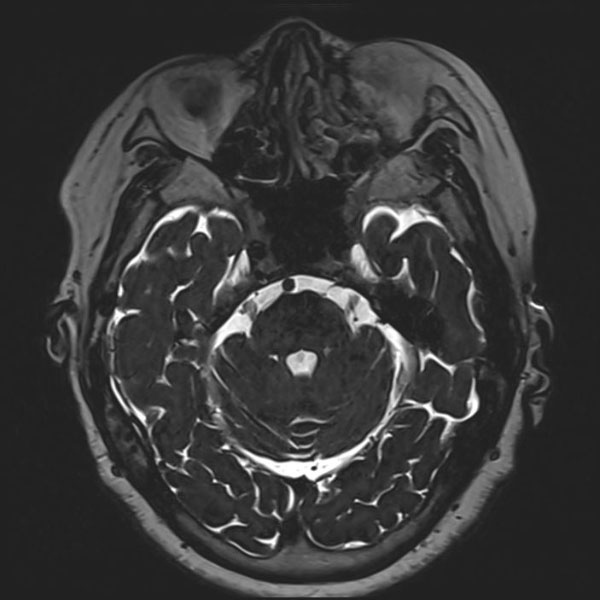

症例 '26年4月

No.

589

病名

'26年4月

70代

左三叉神経痛

手術前